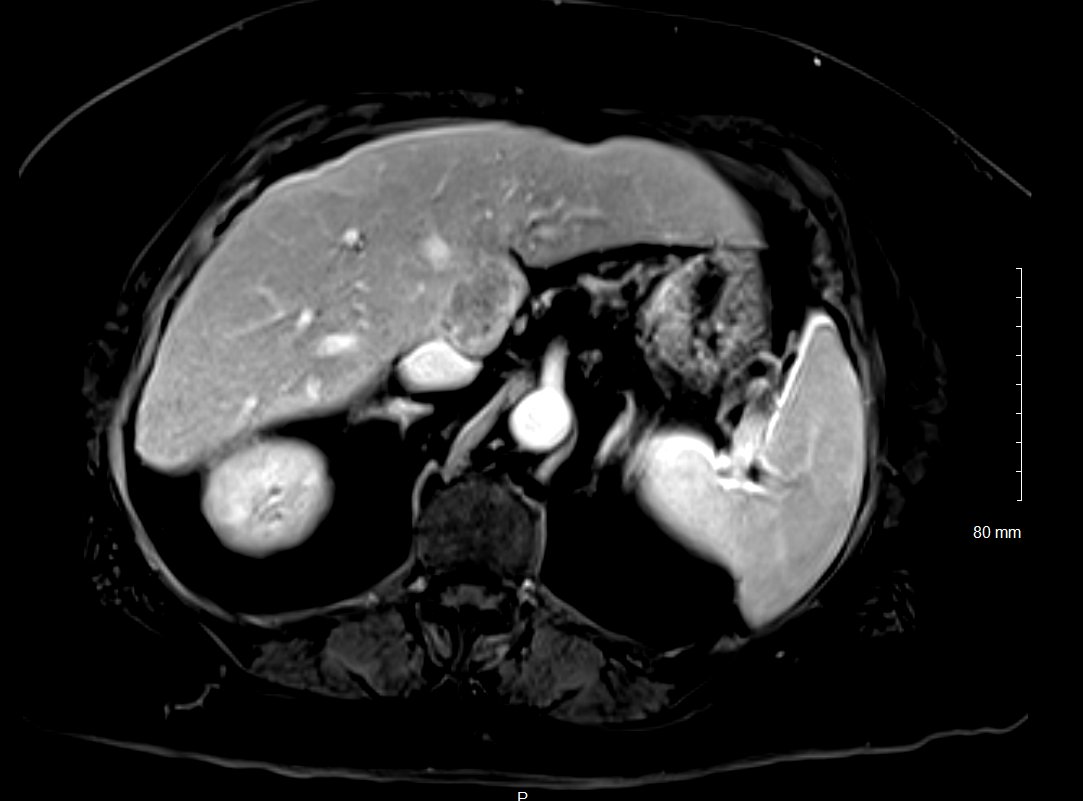

New study @AnnalsofIM bit.ly/2Km3KYu by @DrTalenfeld @WeillCornell: Percutaneous ablation for T1a #renalcancer has similar 5-year survival rates to radical nephrectomy but with far fewer 30-day complications and less #kidneyfailure.